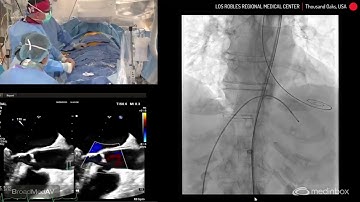

Download lagu TAVI Using A Navitor SEV secara gratis hanya untuk keperluan promosi. Dukung artis favorit kamu dengan membeli musik original di iTunes atau platform resmi lainnya.